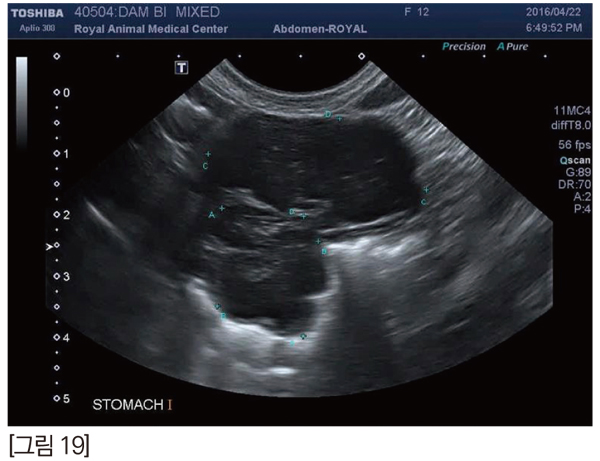

이 종괴는 초음파 검사상 위벽을 중심으로 위 내강과 바깥쪽으로 돌출된 형태로 확인 되었으며, 인접한 림프절 종대는 관찰되지 않았습니다. [그림 19]